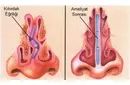

Burun Kıkırdak Eğriliği Belirtileri ve Tedavisi

Burun kıkırdak eğriliği, burun septumundaki bozuklukların neden olduğu rahatsız edici bir durumdur. Belirtileri arasında burun tıkanıklığı, baş ağrıları ve uyku apnesi yer alır. Tedavi seçenekleri, ilaçlardan cerrahi müdahalelere kadar değişir. Uzman görüşü, en uygun çözüm için önemlidir.

Burun Kıkırdak Eğriliği Belirtileri ve Tedavisi Burun kıkırdak eğriliği, burun septumunun (burun ortasındaki yapı) anormal bir şekilde eğrilmesi veya şekil bozukluğu olarak tanımlanabilir. Bu durum, bireylerin yaşam kalitesini etkileyen ve çeşitli sağlık sorunlarına yol açabilen önemli bir rahatsızlıktır. Burun kıkırdak eğriliği, genellikle doğuştan gelir, ancak travma veya yaralanmalar sonucu da gelişebilir. Burun Kıkırdak Eğriliğinin Belirtileri Burun kıkırdak eğriliği, birçok belirtiyle kendini gösterebilir. Bu belirtiler kişiden kişiye değişebilir, ancak genel olarak aşağıdaki semptomlar sıklıkla görülmektedir:

Bu belirtiler, bireyin günlük yaşamını olumsuz etkileyebilir ve bazen daha ciddi sağlık sorunlarına yol açabilir. Burun Kıkırdak Eğriliğinin Nedenleri Burun kıkırdak eğriliğinin nedenleri genellikle aşağıdaki gibi sıralanabilir:

Tanı Yöntemleri Burun kıkırdak eğriliğinin tanısı, genellikle bir kulak burun boğaz uzmanı tarafından yapılır. Tanı sürecinde kullanılan yöntemler şunlardır:

Tedavi Seçenekleri Burun kıkırdak eğriliği tedavisi, hastanın semptomlarına ve durumun ciddiyetine bağlı olarak değişiklik gösterir. Tedavi yöntemleri şunlardır:

Sonuç Burun kıkırdak eğriliği, birçok bireyi etkileyen yaygın bir durumdur. Belirtiler, yaşam kalitesini olumsuz etkileyebilir ve tedavi edilmediği takdirde daha ciddi sorunlara yol açabilir. Bu nedenle, burun kıkırdak eğriliği belirtileri yaşayan kişilerin bir uzmana başvurması önemlidir. Tedavi seçenekleri sayesinde, bireyler bu rahatsızlıktan kurtulabilir ve daha sağlıklı bir yaşam sürdürebilirler. Ek olarak, burun kıkırdak eğriliği ile ilgili daha fazla bilgi edinmek isteyen bireylerin, kulak burun boğaz uzmanları ile iletişime geçmeleri önerilmektedir. Bu uzmanlar, durumun ciddiyetini değerlendirerek en uygun tedavi yöntemini belirlemede yardımcı olabilirler. |